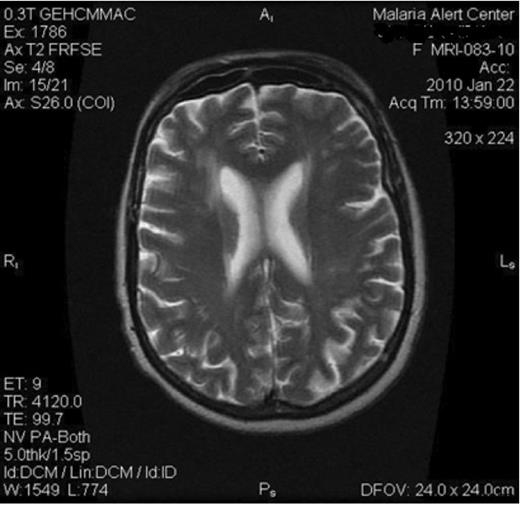

The histopathology microscopic examination of the lesion demonstrated Tinea solium worms with multiple foci of dystrophic calcification and reactive plasma cellular infiltrate with extensive fibrosis, where as MRI ruled out brain involvement and clearly delineated the location, size and extent of the colossal cysticercosis lesion of the neck (Fig.2). Biochemical and haematological parameters were normal.

MRI of the brain revealed no masses which generally ruled out brain involvement (Neurocysticercosis)